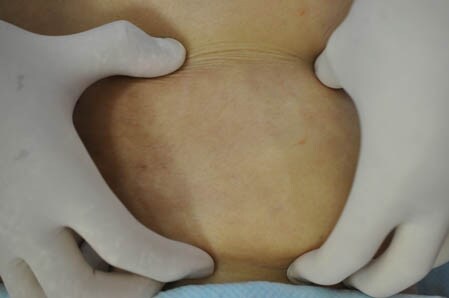

上腹部の皮下脂肪の状態を

手術直前と直後で比較して見てみましょう。

↓ ↓ ↓

上記の画像の部分をつまんでみましょう。